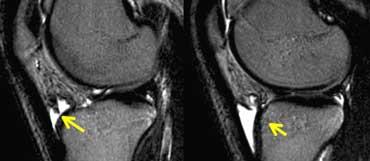

Ca lâm sàng bên trái là không ổn định vì hai lý do:

– Các nang nhỏ ở nền tổn thương (mũi tên đỏ)

– Quan trọng hơn là có dịch ở nền tổn thương (mũi tên xanh)

Lưu ý rằng lớp dịch này khác với AVN, nơi dịch nằm giữa sụn và xương.

Viêm xương sụn bóc tách không ổn định. Dấu hiệu duy nhất có giá trị để chẩn đoán OD không ổn định là dịch (mũi tên vàng), không phải phù tủy hay gián đoạn bề mặt xương sụn (mũi tên xanh lá).

Các dấu hiệu không có giá trị trong việc phân biệt OD ổn định và không ổn định bao gồm:

– Phù tủy xương (có thể gặp trong cả hai trường hợp)

– Gián đoạn bề mặt xương sụn.

Vì vậy, ca lâm sàng bên trái là không ổn định vì có dịch ở nền tổn thương.

Ca lâm sàng bên trái cho thấy viêm xương sụn bóc tách với phù tủy xương và gián đoạn bề mặt xương sụn.

Tuy nhiên, vì không có dịch, chúng ta không thể xác định đây là tổn thương ổn định hay không ổn định.

Trong phẫu thuật, tổn thương viêm xương sụn bóc tách được xác nhận là ổn định.

Trong những trường hợp không thể xác định tổn thương ổn định hay không ổn định, chụp MRI khớp có thuốc tương phản từ (MR-arthrogram) rất có giá trị.

Chúng ta tìm kiếm dấu hiệu Gadolinium thấm vào xung quanh tổn thương xương sụn.